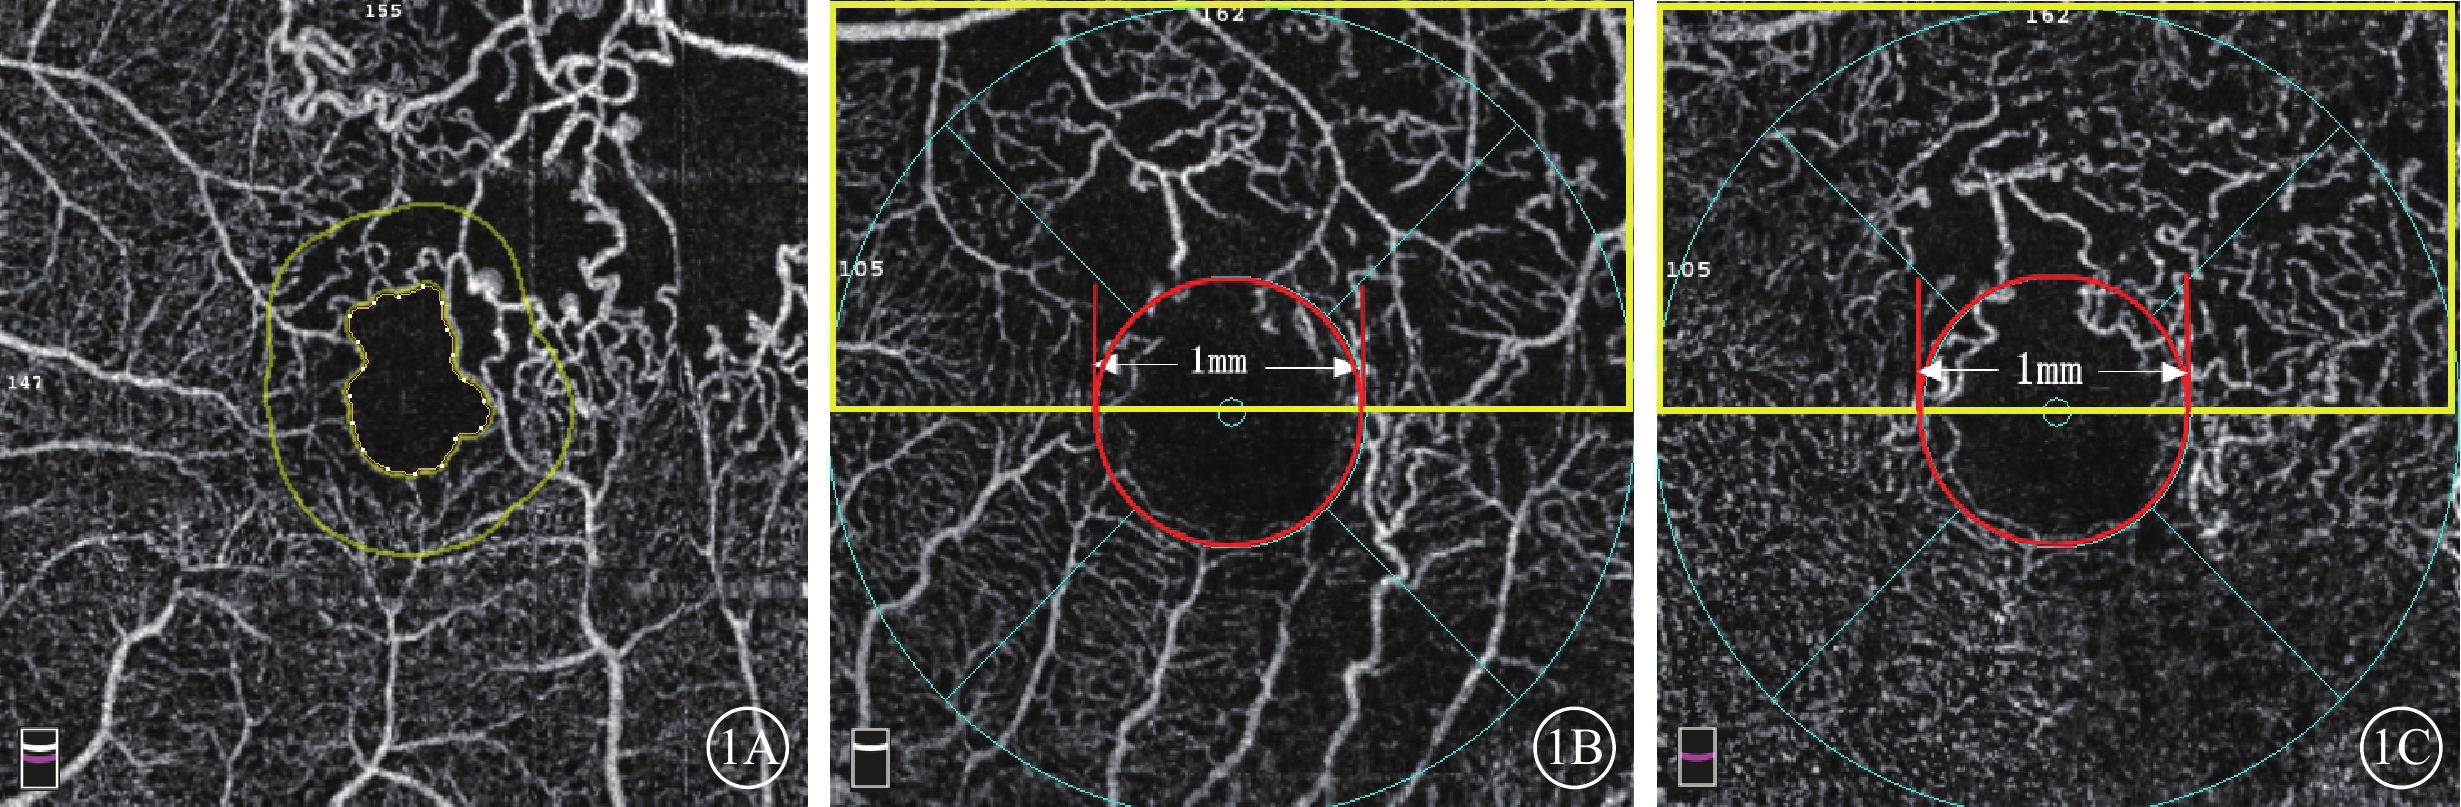

采用美國Optovue公司RTVue-XR Avanti OCT儀行黃斑區OCTA檢查。檢查由同一位熟練醫生獨立操作完成。掃描程序AngioVue Retina,掃描范圍3 mm×3 mm,A掃描為70 000次/s,光源波長840 nm,頻寬50 nm。每次A掃描包含304×304條B掃描線。所采集數據采用系統自帶軟件進行分析,并自動合成4張不同層面OCTA圖像,即SCP、DCP、外層視網膜及脈絡膜毛細血管層。采用設備自帶軟件(OCTA血流量化標準2.0版)測量并計算全層視網膜FAZ面積、PERIM、非圓度指數(AI)以及FAZ范圍300 μm寬度內的血流密度(FD-300)(圖1A),中心凹視網膜厚度(CRT),中心凹SCP視網膜血流密度(SFVD)、中心凹DCP視網膜血流密度(DFVD),BRVO病灶所在區域SCP半側視網膜血流密度(SHVD)、DCP半側視網膜血流密度(DHVD)(圖1B,1C)。SCP為內界膜(ILM)上3 μm至內叢狀層(IPL)下15 μm,包含視神經纖維層和節細胞層;DCP為IPL下15~70 μm,主要包含內核層。全層視網膜是從ILM至內叢狀層邊界之間的視網膜各層;水腫腔位于ILM與IPL之間導致斷面分層發生錯誤時,給予手動調整并記錄調整后的數據。AI=PERIM/等面積標準圓周長。75只眼中,28只眼(37.33%)FAZ面積自動識別區域與FAZ真正呈現區域不符,給予手動調整并記錄(圖2)。

圖1

FAZ面積、FERIM、FD-300、黃斑區血流密度測量示意圖。1A示FAZ面積(內圈不規則黃色線內區域)、FERIM(內圈不規則黃色線周長)、FD-300(黃色線內外圈之間環形區域);1B、1C分別示SCP、DCP.SFVD(紅色線圈內區域),SHVD(黃色方框內)

圖1

FAZ面積、FERIM、FD-300、黃斑區血流密度測量示意圖。1A示FAZ面積(內圈不規則黃色線內區域)、FERIM(內圈不規則黃色線周長)、FD-300(黃色線內外圈之間環形區域);1B、1C分別示SCP、DCP.SFVD(紅色線圈內區域),SHVD(黃色方框內)

采用美國Optovue公司RTVue-XR Avanti OCT儀行黃斑區OCTA檢查。檢查由同一位熟練醫生獨立操作完成。掃描程序AngioVue Retina,掃描范圍3 mm×3 mm,A掃描為70 000次/s,光源波長840 nm,頻寬50 nm。每次A掃描包含304×304條B掃描線。所采集數據采用系統自帶軟件進行分析,并自動合成4張不同層面OCTA圖像,即SCP、DCP、外層視網膜及脈絡膜毛細血管層。采用設備自帶軟件(OCTA血流量化標準2.0版)測量并計算全層視網膜FAZ面積、PERIM、非圓度指數(AI)以及FAZ范圍300 μm寬度內的血流密度(FD-300)(圖1A),中心凹視網膜厚度(CRT),中心凹SCP視網膜血流密度(SFVD)、中心凹DCP視網膜血流密度(DFVD),BRVO病灶所在區域SCP半側視網膜血流密度(SHVD)、DCP半側視網膜血流密度(DHVD)(圖1B,1C)。SCP為內界膜(ILM)上3 μm至內叢狀層(IPL)下15 μm,包含視神經纖維層和節細胞層;DCP為IPL下15~70 μm,主要包含內核層。全層視網膜是從ILM至內叢狀層邊界之間的視網膜各層;水腫腔位于ILM與IPL之間導致斷面分層發生錯誤時,給予手動調整并記錄調整后的數據。AI=PERIM/等面積標準圓周長。75只眼中,28只眼(37.33%)FAZ面積自動識別區域與FAZ真正呈現區域不符,給予手動調整并記錄(圖2)。

圖1

FAZ面積、FERIM、FD-300、黃斑區血流密度測量示意圖。1A示FAZ面積(內圈不規則黃色線內區域)、FERIM(內圈不規則黃色線周長)、FD-300(黃色線內外圈之間環形區域);1B、1C分別示SCP、DCP.SFVD(紅色線圈內區域),SHVD(黃色方框內)

圖1

FAZ面積、FERIM、FD-300、黃斑區血流密度測量示意圖。1A示FAZ面積(內圈不規則黃色線內區域)、FERIM(內圈不規則黃色線周長)、FD-300(黃色線內外圈之間環形區域);1B、1C分別示SCP、DCP.SFVD(紅色線圈內區域),SHVD(黃色方框內)